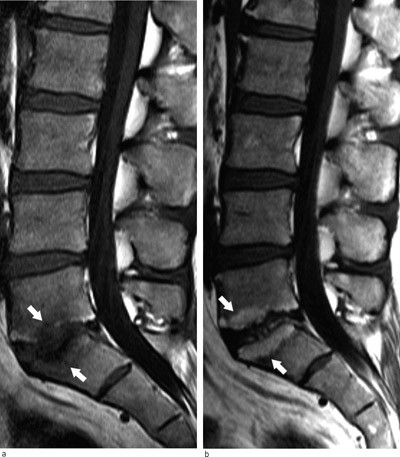

Inn mot degenerative mellomvirvelskiver kan man på MR se signalforandringer i dekkplatene og i beinmargen i tilstøtende virvelcorpora. Dette kalles Modic-forandringer og er vanligst i nivåene L4/L5 og L5/S1 (21). Det er to hovedtyper av disse beinmargsforandringene. Type 1 har lavt signal på T1-vektede bilder og høyt signal på T2-vektede som uttrykk for en inflammatorisk reaksjon med beinmargsødem. Type 2 har høyt T1-signal og høyt T2-signal som tegn på fettomdanning av den røde beinmargen.

I en systematisk litteraturoversikt var median prevalens av Modic-forandringer 43 % hos pasienter med smerter lavt i ryggen og/eller isjias, men bare 6 % i normalpopulasjonen (22). En dansk populasjonsstudie av 40-åringer viste at det var sammenheng mellom Modic-forandringer og forekomst av uspesifikke smerter lavt i ryggen (15). Slike beinmargsforandringer er ikke stabile. Over tid kan type 1 overgå til type 2, men de kan også forsvinne av seg selv (23) (fig 4). Den kliniske betydningen av Modic-forandringer er fortsatt usikker. Eventuelle terapeutiske konsekvenser undersøkes i pågående studier.